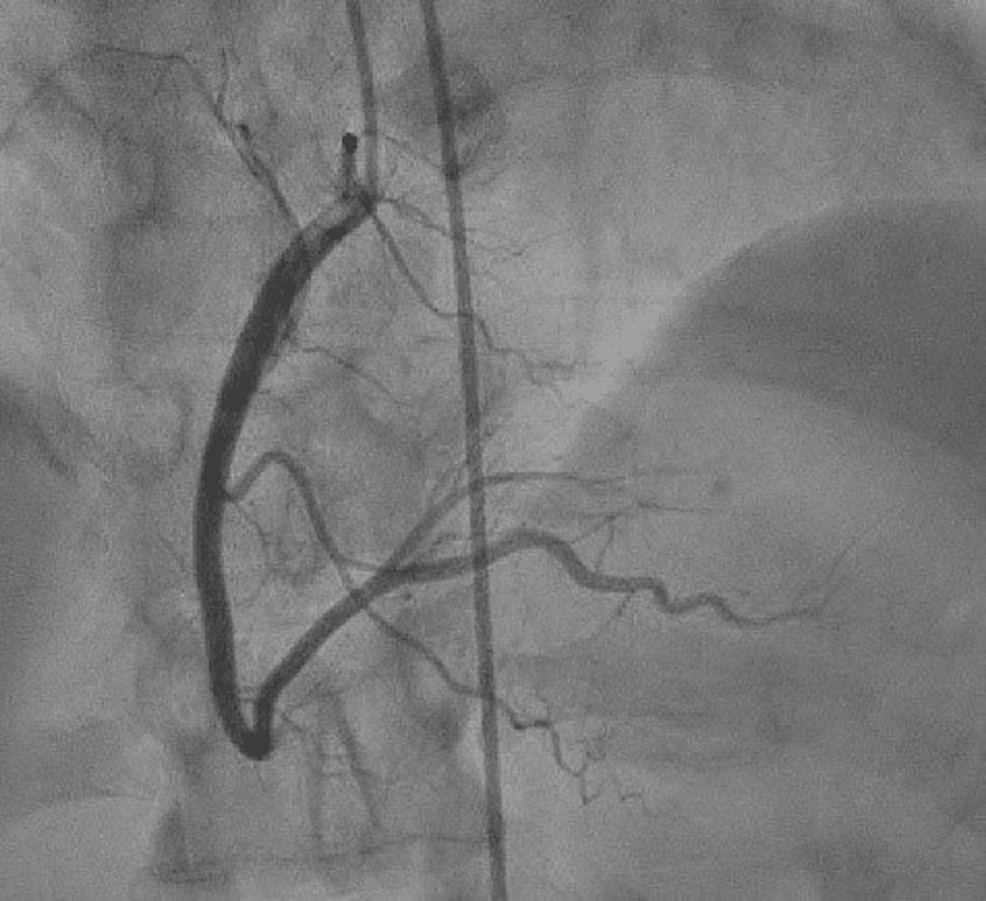

Cardiac catheterization performed on 28 October 2022, which showed

Cardiac catheterization performed on 28 October 2022, which showed Cardiac Catheterization Ejection Fraction A normal heart’s ejection fraction is between 55 and 70 percent. Ejection fraction is measured as a percentage of the total amount of blood in your heart that is pumped out with each heartbeat. 10k+ visitors in the past month When the heart squeezes, it's. A normal ejection fraction is 50 percent or. Ejection fraction is the fraction of the. Cardiac Catheterization Ejection Fraction.